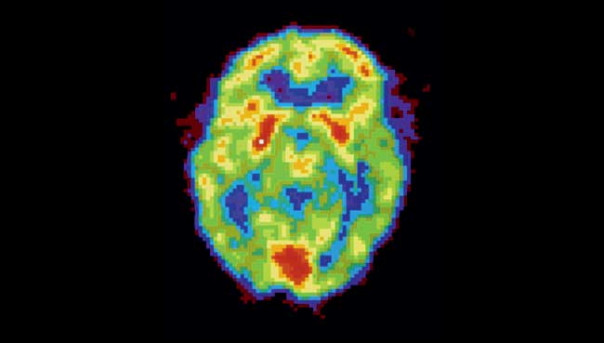

Активность мозга сильно различается не только во время бодрствования и сна — есть множество промежуточных состояний, которые можно различить во время позитронно-эмиссионной томографии.

НЕСПЯЩИЙ МОЗГ. Активность мозга в этой стадии (красные зоны на снимке) похожа на то, что происходит в REM-сне